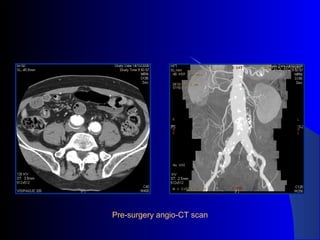

The document discusses the clinical application of the Endurant stent graft system in treating aorto-bisiliac aneurysms, detailing procedures performed on two male patients aged 72 and 73. Each patient had a history of dyslipidemia and carotid atherosclerosis, with procedures involving the bilateral bell bottom technique and the use of coils and fibrin glue. It includes pre-surgery imaging, intrasurgery angiography, and follow-up control scans to monitor outcomes.